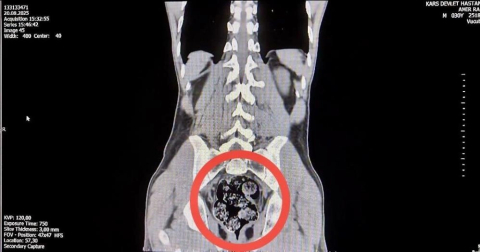

İl Emniyet Müdürlüğü'ne getirilen ve durumundan şüphelenilen kuryelerden Shekarbaghanı, detaylı arama için Kars Harakani Devlet Hastanesi'ne götürüldü. Hastanede yapılan emar ve röntgen kontrollerinde şüphelinin makatında cisim olduğu belirlendi. Yapılan cerrahi müdahalede, şüphelinin makatından 7 parça halinde 203,02 gram metamfetamin çıkarıldı.